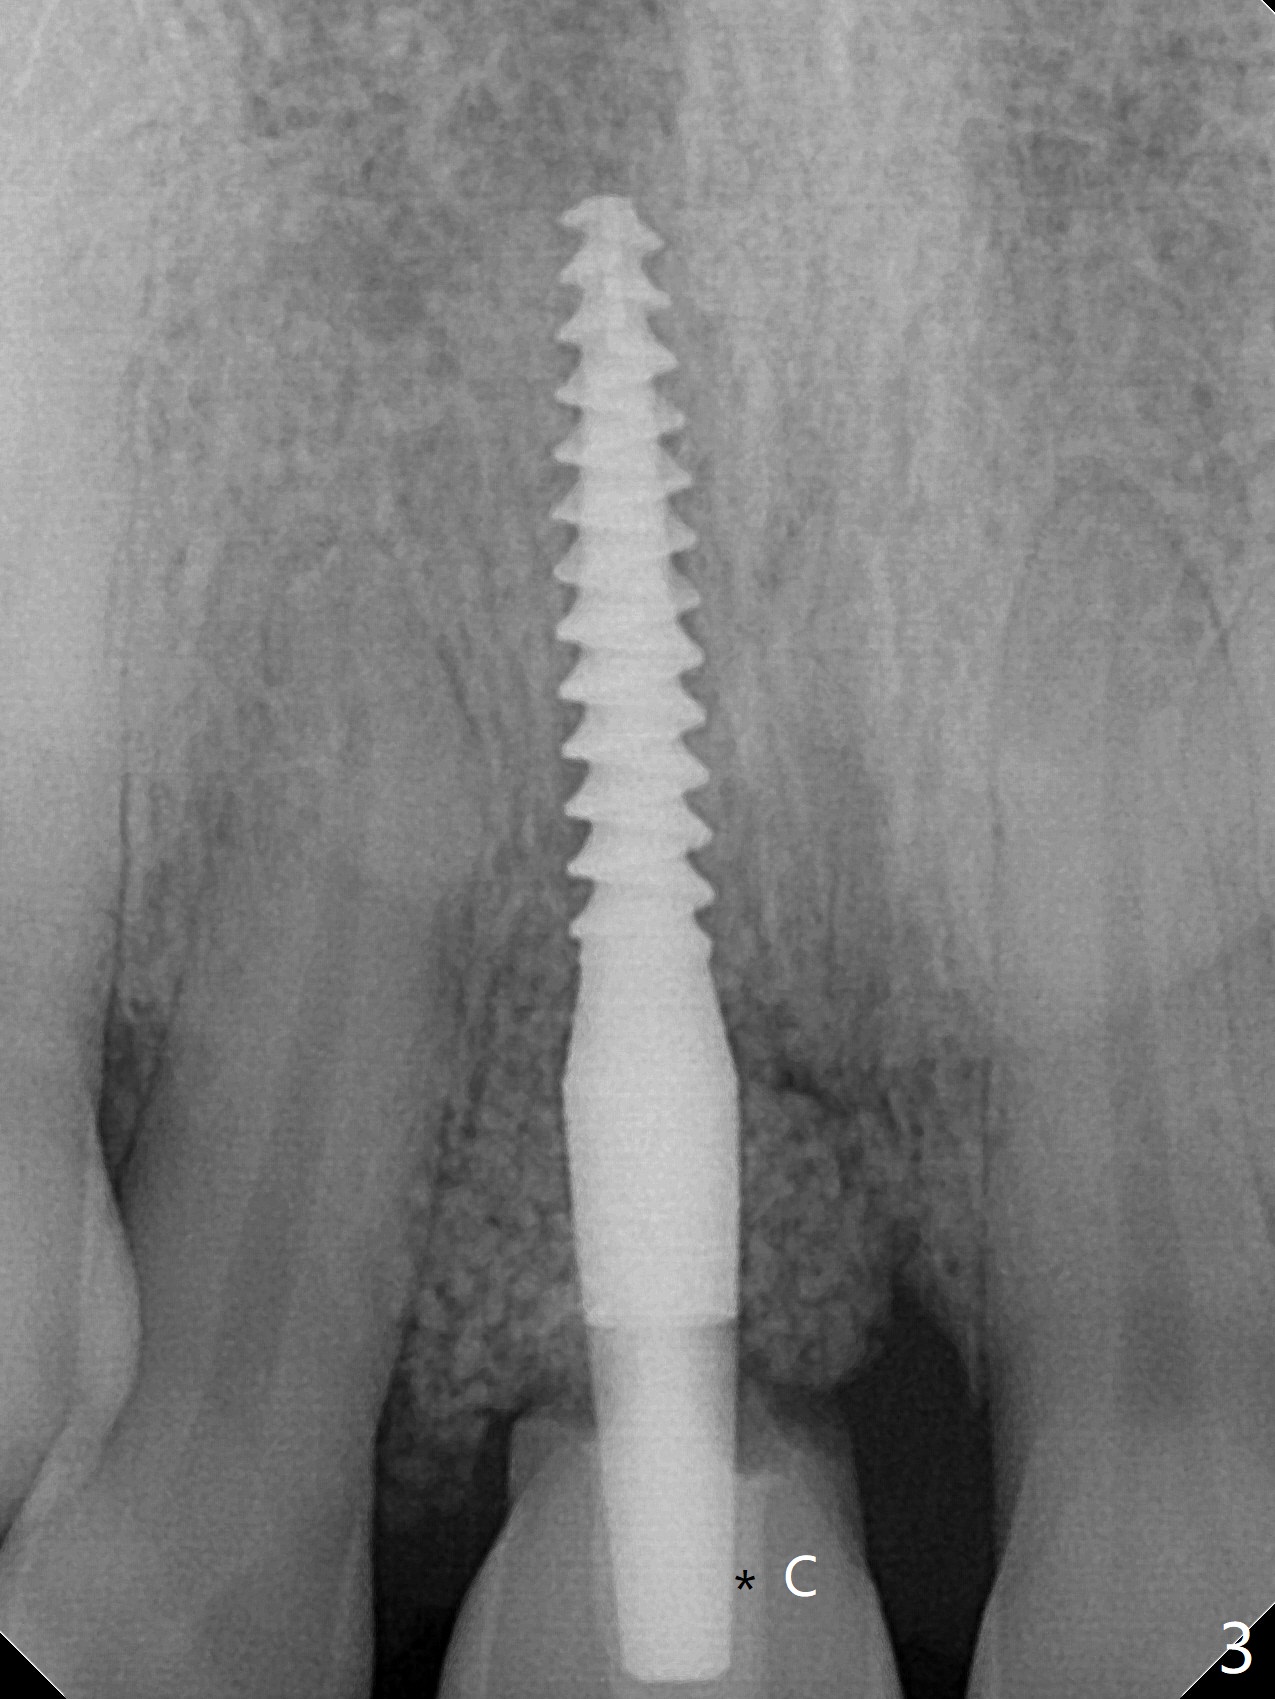

50岁女8号牙远中颊侧冠方移位(图一),牙根暴露(*),前磨牙-前磨牙开合,腭侧牙龈红肿。拔除清创后,使用导板钻洞,徒手植入2.5x13毫米一段式植体,首先将PRF膜插入腭侧,剩余牙槽窝空间植入粘性骨粉(图二:*)。截断拔除牙齿,牙冠掏空,反复调整牙冠长度,使用流动性树脂(flowable composite,图三:*)衬里固定牙冠(C),恰好PRF封闭远中颊侧牙槽窝开口(图四),自然牙冠和一段式植体配合,形成最佳emergency profile,最后牙周敷料进一步封闭牙槽窝(图五),防止骨粉早期脱落,不必担忧敷料不透气。腭侧牙龈红肿(图六)。服用Augmentin两天,患处没有触痛了(图七)。术后九天颊侧牙龈继续延长(图八).